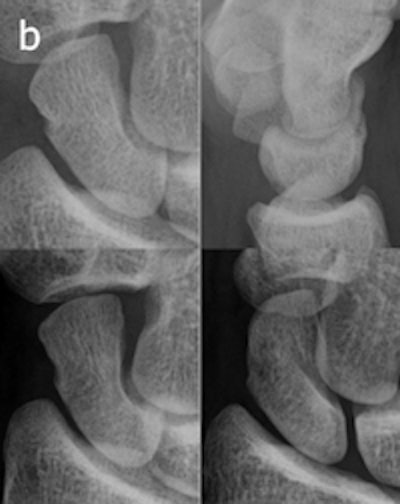

A 20-year-old man who had initial negative wrist and scaphoid radiographs. The follow-up radiograph (a) was normal. No fractures were observed in enlargements of the wrist radiographs and two scaphoid views (b). All images reprinted with permission of Springer Publishing.

Injuries were stabilized in a plaster cast for two weeks. One patient declined to participate in the trial. Follow-up imaging for the remaining 35 patients was performed at a separate site at some distance away from the ER, where CR and tomosynthesis could be performed in sequence. In actual practice, the optimal use of musculoskeletal tomosynthesis will be found by placing the equipment in the ER, Geijer noted in an e-mail to AuntMinnie.com.